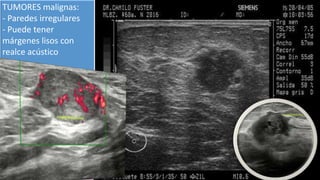

TUMORES malignas:

- Paredes irregulares

- Puede tener

márgenes lisos con

realce acústico

TUMORES malignas: - Paredesirregulares - Puede tener márgenes lisos con realce acústico